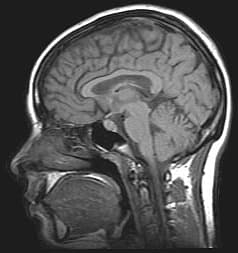

Idiopathic intracranial hypertension (IIH), previously known as pseudotumor cerebri and benign intracranial hypertension, is a condition characterized by increased intracranial pressure (pressure around the brain) without a detectable cause. The main symptoms are headache, vision problems, ringing in the ears, and shoulder pain. Complications may include vision loss. This condition is idiopathic, meaning there is no known cause. Risk factors include being overweight or a recent increase in weight. Tetracycline may also trigger the condition. The diagnosis is based on symptoms and a high opening pressure found during a lumbar puncture with no specific cause found on a brain scan. Treatment includes a healthy diet, salt restriction, and exercise. The medication acetazolamide may also be used along with the above measures. A small percentage of people may require surgery to relieve the pressure. About 2 per 100,000 people are newly affected per year. The condition most commonly affects women aged 20–50. Women are affected about 20 times more often than men. The condition was first described in 1897. The most common symptom of IIH is severe headache, which occurs in almost all (92–94%) cases. It is characteristically worse in the morning, generalized in character and throbbing in nature. It may be associated with nausea and vomiting. The headache can be made worse by any activity that further increases the intracranial pressure, such as coughing and sneezing. The pain may also be experienced in the neck and shoulders. Many have pulsatile tinnitus, a whooshing sensation in one or both ears (64–87%); this sound is synchronous with the pulse. Various other symptoms, such as numbness of the extremities, generalized weakness, pain and/or numbness in one or both sides of the face, loss of smell, and loss of coordination, are reported more rarely; none are specific for IIH. In children, numerous nonspecific signs and symptoms may be present. The increased pressure leads to compression and traction of the cranial nerves, a group of nerves that arise from the brain stem and supply the face and neck.